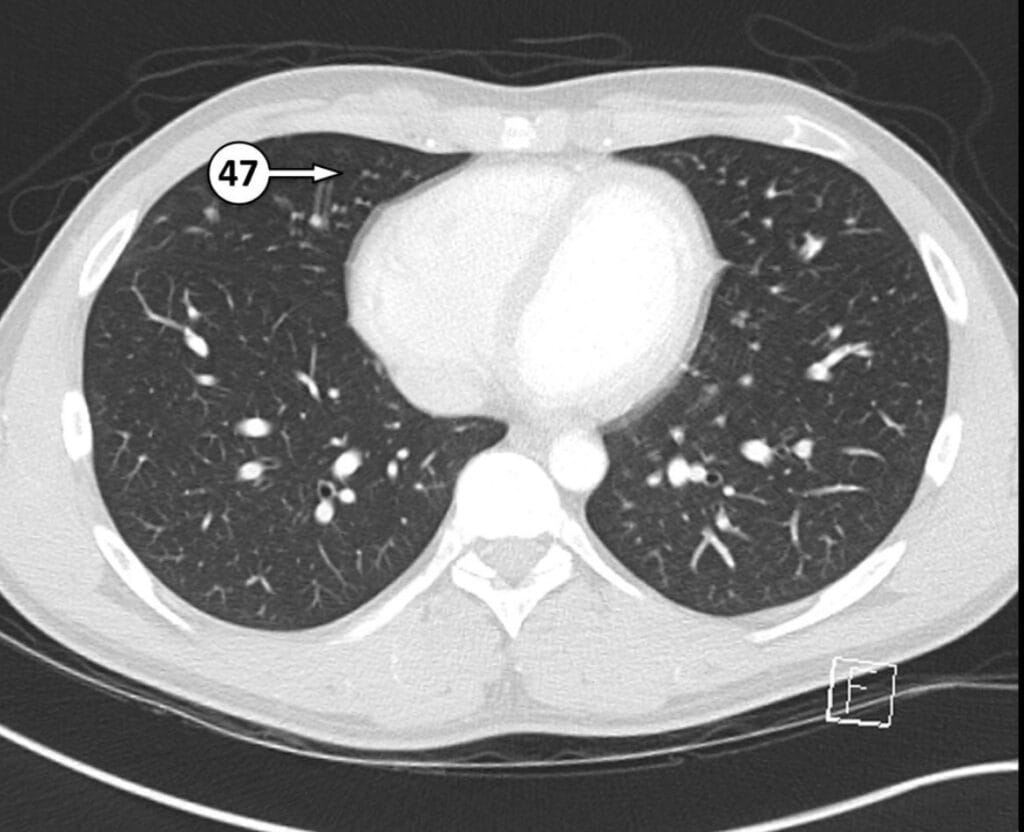

47. medial segment of RML